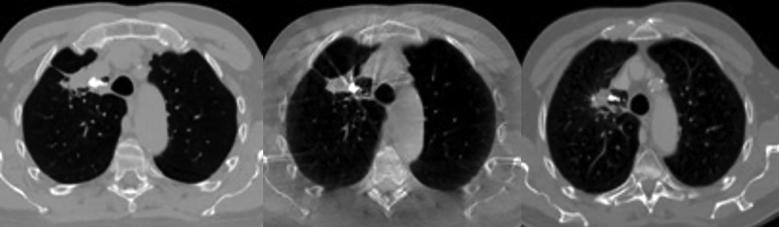

Safety and clinical feasibility of injecting a novel liquid fiducial marker for use in image guided radiotherapy in 15 patients with non-small cell lung cancer are reported. No major safety or toxicity issues were encountered. Markers present at start of radiotherapy remained visible in cone beam computed tomography and fluoroscopy images throughout the treatment course and on computed tomography images during follow-up (0-38 months). Marker volume reduction was seen until 9 months after treatment, after which no further marker breakdown was found. No post-treatment migration or marker related complications were found.

报告了15例非小细胞肺癌患者注射一种用于图像引导放射治疗的新型液体基准标记物的安全性和临床可行性。未遇到重大安全或毒性问题。放疗开始时存在的标记物在整个治疗过程中的锥束计算机断层扫描和荧光透视图像中以及随访期间(0 - 38个月)的计算机断层扫描图像中均可见。治疗后9个月前可见标记物体积减小,此后未发现标记物进一步分解。未发现治疗后迁移或与标记物相关的并发症。